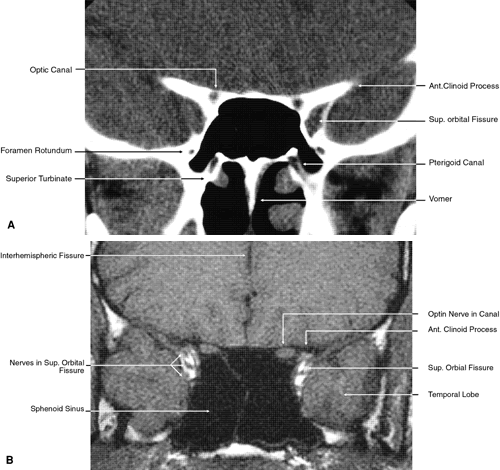

Fig. 17. Coronal images through anterior orbit. A. Computed tomography scan. B. T1-weighted magnetic resonance imaging.

Fig. 18. Coronal images through midglobe. A. Computed tomography scan. B. T1-weighted magnetic resonance imaging.

Fig. 19. Coronal images through midorbit posterior to the globe. A. Computed tomography scan.B. T1-weighted magnetic resonance imaging.

Fig. 20. Coronal images through orbital apex. A. Computed tomography scan. B. T1-weighted magnetic resonance imaging. C. Anatomic section of a cadaver head at the level of the orbital apex.

The globe is shown in Figure 12. The orbit and periorbital structures are shown in Figures 13 through 16, and the optic canal is shown in Figures 17 through 26. The cavernous sinus and optic chiasm are shown in Figures 27 and 28, and the posterior visual pathway and cranial nerves are shown in Figures 29 through 33.